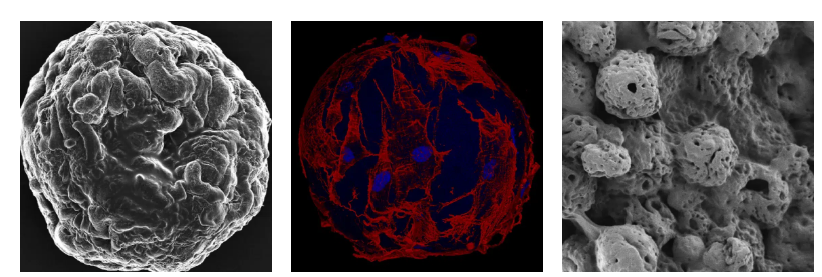

在当前的研究中,研究团队利用3D打印技术制造了小型冰球,并将它们植入小鼠皮下。结果显示,这项技术有潜力用于培养患者自身细胞,这些细胞可以从最小的皮肤活检样本中获得,然后3D打印成移植用的组织,并应用于伤口治疗。

Johan Junker解释道:“我们观察到细胞不仅存活下来,而且显然它们能够产生构成新真皮所需的各种成分。此外,移植物中形成了血管,这对于组织在体内存活是至关重要的。我们相信这种材料非常有前景。”

在测试中,植入小鼠皮肤下的3D打印冰球展示了细胞存活、真皮构建活动以及血管形成——这些是组织存活的关键指标。